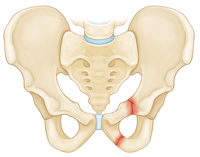

Less commonly, a fracture may occur when a piece of the ischium bone tears away from the site where the hamstring muscles attach to the bone. This type of fracture is called an avulsion fracture and it is most common in young athletes who are still growing. An avulsion fracture does not usually make the pelvis unstable or injure internal organs.

Superior and inferior pubic ramus fracture